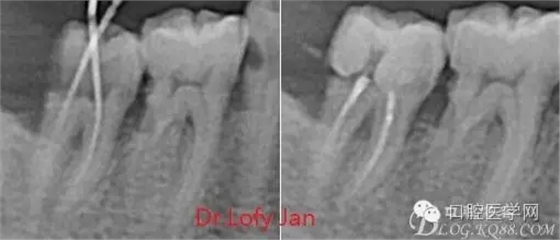

曲面斷層片在未試尖根管治療中的病例整理

前言:自己做的一些曲面斷層片在未試尖根管治療中的病例整理,發(fā)現(xiàn)問題很多包括自身的,技術(shù)的,還有設(shè)備的問題,予以總結(jié)整理并期待進(jìn)一步提高。

根管治療術(shù)是牙體牙髓疾病治療中最復(fù)雜和最關(guān)鍵的治療項(xiàng)目。根管充填材料抵達(dá)根尖、并能嚴(yán)密堵塞根尖孔,是確保根管治療效果的關(guān)鍵指標(biāo)。為了保證根管充填到位,醫(yī)生需要在術(shù)前照牙片以了解牙根根管的數(shù)量、彎曲程度和長(zhǎng)度,在術(shù)中有時(shí)需要插針照牙片來精確測(cè)量根管長(zhǎng)度,術(shù)后必須照牙片以確定是否根管充填到位,如果欠填或超填,就需要重新充填、重新照牙片確認(rèn),直到根管充填到位。所以,在患者接受根管治療時(shí)有時(shí)會(huì)反復(fù)照牙片。

病例分析:曲面斷層片在x線輔助診斷與檢查中目前大多數(shù)文獻(xiàn)和著作都建議只能作為初診拍片檢查手段,不能作為終末疾病的確診與手術(shù)療效的評(píng)價(jià)指標(biāo),臨床大部分中小型門診都因?yàn)樵O(shè)備不齊全導(dǎo)致信息偏差很大。